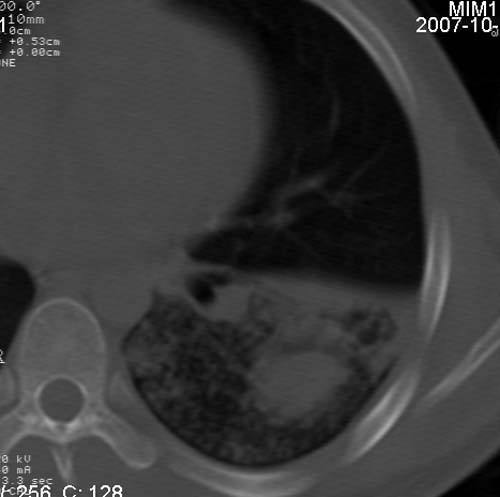

男,21岁,咳嗽、胸闷、乏力伴多汗二十余日、无明显发烧。患者一般情况好,为初三学生。

右肺上叶前段及左肺下叶多形性病变伴厚壁空洞,周边示树芽征.左肺下叶不张改变.

考虑;肺结核,不除外左肺下叶支气管内膜结核.

双肺继发性肺结核伴左侧空洞形成!不除外合并霉菌感染!(双肺多发病灶,左侧病灶形成空洞,并空洞内见壁结节。建议改变体位,观察空洞内结节情况,以便排除霉菌感染!)

左下肺实变能给出合理解释吗?